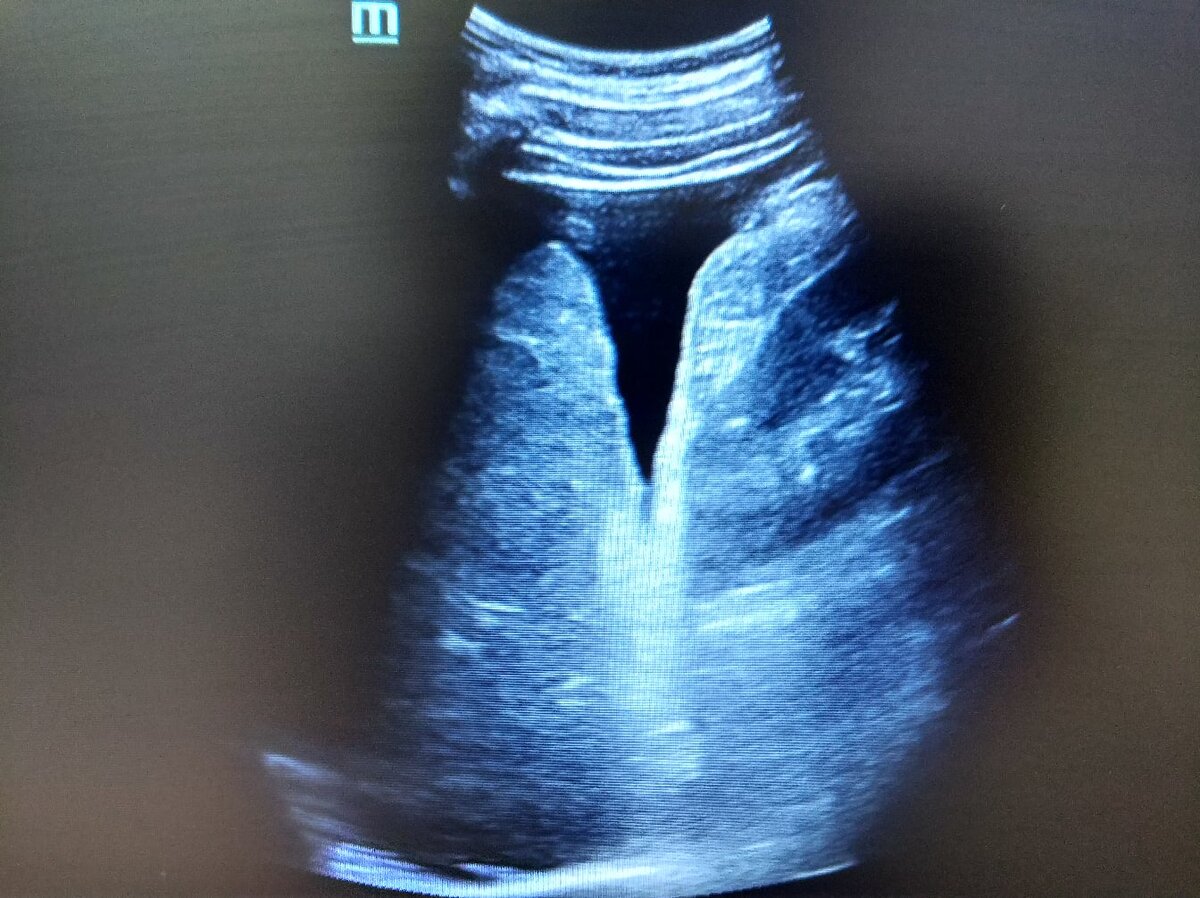

❓Видно ли цирроз на УЗИ❓

Именно так, видно.

🖼️Типичные проявления: симптом пунктира, выпот, высокий цирротический индекс.

🖼️Typical manifestations: dotted symptom, effusion, high cirrhotic index.